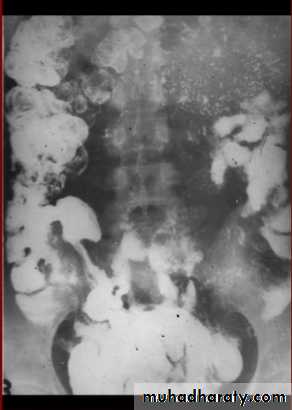

Multiple dilated small bowel loops are present. The valvulae conniventes

are thin and straight and closely stacked together.